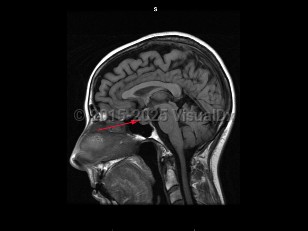

A craniopharyngioma is a brain tumor arising from pituitary embryonic tissue. It is typically suprasellar and has solid and cystic components. Age of onset can occur in childhood (about age 5-15) or adulthood (about age 50-70). There are adamantinomatous, papillary, and mixed types. Adamantinomatous tumors are more common in children and papillary tumors are more common in adults. A Rathke cleft cyst may develop from Rathke pouch if the pouch does not close normally.

Craniopharyngiomas are usually slow growing, and symptoms arise from compression of surrounding structures or increased intracranial pressure. Presenting symptoms include visual loss (most commonly superior temporal quadrantanopsia), headache, hormonal imbalances leading to delayed puberty in children, amenorrhea, hypersomnia, diabetes insipidus, and/or decreased libido. These tumors are usually benign with a good prognosis, but often recur when resection is incomplete.